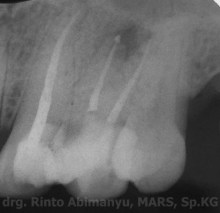

Dari hasil pemeriksaan radiografis terlihat kavitas sudah mengenai pulpa, dan ada lesi periapeks..

Radiografis gigi 24